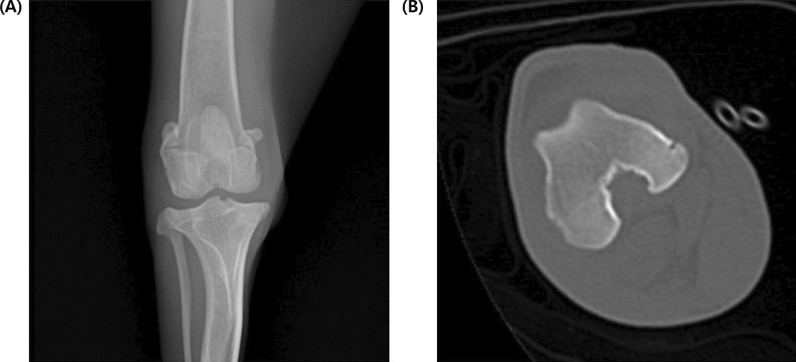

Background: This study aimed to establish an image evaluation grading criteria for experimental stifle joint osteoarthritis (OA) in anterior cruciate ligament transection induced OA beagle dog models. The severity of OA was assessed using X-ray and computed tomography (CT) imaging.

Conclusions: The developed grading criteria based on radiographic evaluation correlated with clinical assessments. The study also employed CT imaging to enhance the accuracy and sensitivity of early-stage OA change detection in the stifle joint. However, further studies with larger sample sizes and multiple evaluators are recommended for the validation and generalizability of this grading system. These established image evaluation grading criteria can help evaluate and monitor the efficacy of interventions and changes in OA lesions in canine models.